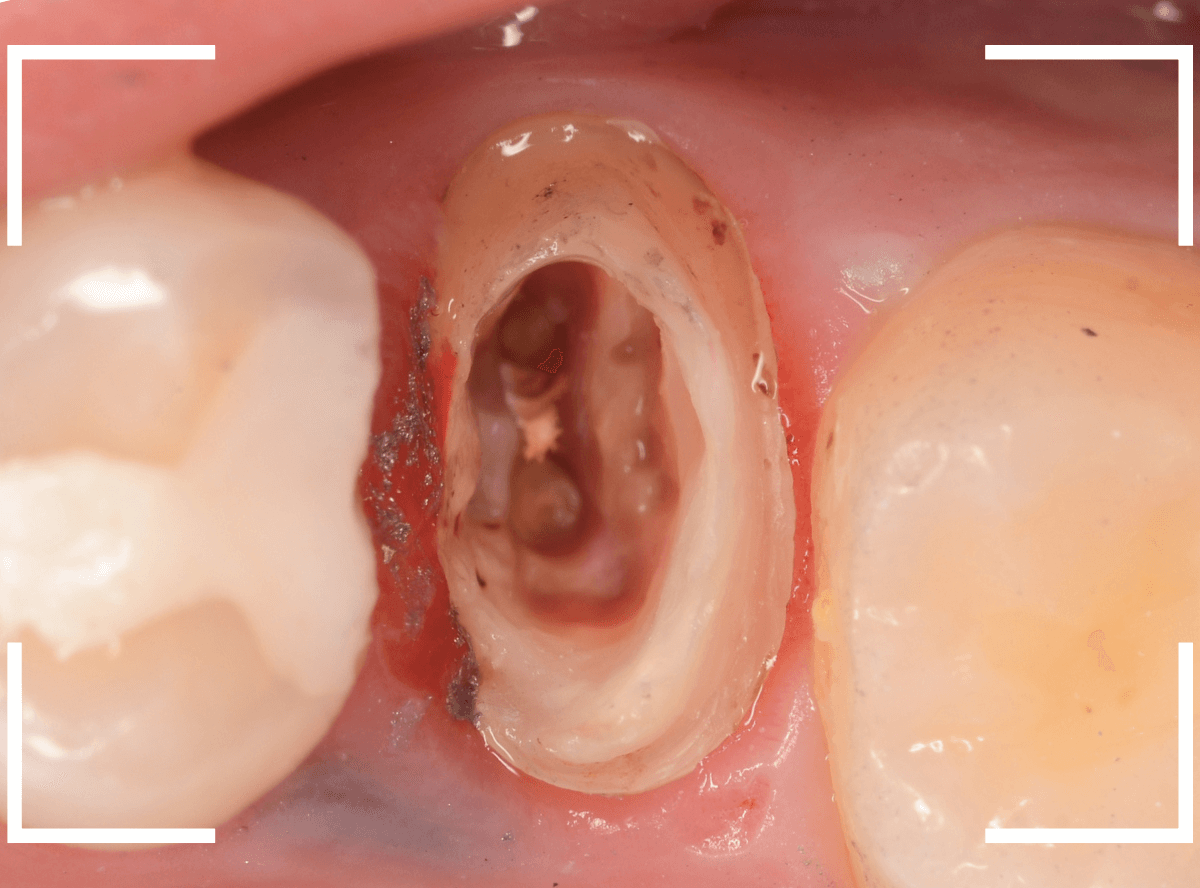

患者さんに状況を説明し、歯の周りの歯肉を麻酔をして電気メスでトリミングします。

このように歯の際が歯肉からしっかり出てる状況で製作しないと、さし歯はしっかりお口の中で安定しません。

この状態で新しい土台(ファイバー・コア)の型を取ります。

模型上でファイバーコアを製作します。

ファイバーコアをsetし、歯の周りの歯肉が落ち着くまで、仮歯を入れて様子を見ます。